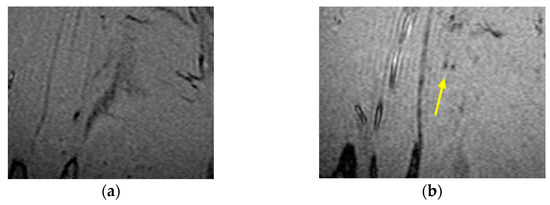

3.1. Results IO-NPs Extraction from 2D Images

3.2. Results of IO-NPs Extraction from Slices of 3D Model